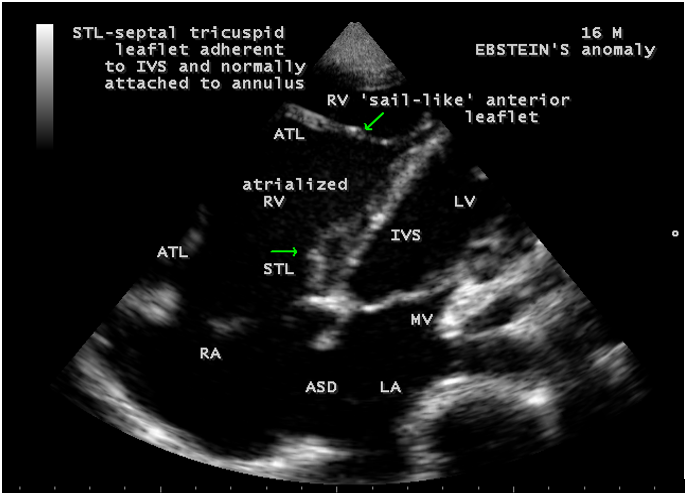

Case 1 (16-year-old cyanotic male with Ebstein’s anomaly) A 16-year-old male presented with cyanosis and he had features of an atrial septal defect such as wide, fixed splitting of second heart sound at left second intercostal space and a grade 2/6 systolic murmur at the lower left sternal border. 2D echocardiography revealed the features of Ebstein’s anomaly such as tethering of septal tricuspid leaflet (STL) to the ventricular wall associated with an ostium secundum type atrial septal defect (ASD) and low mild tricuspid regurgitation jet as shown in Figures 1 to 3

Echocardiographic features Echocardiography is the diagnostic test of choice for Ebstein’s anomaly and the first echocardiographic diagnosis was reported by Lundstrom in 1969. The first diagnostic criteria for Ebstein’s anomaly using a multi-crystal two-dimensional system was defined by Hagan in 1974 [33] and they were able to recognize the apical displacement of the septal tricuspid leaflet and an elongated anterior tricuspid leaflet with increased excursion. The septal leaflet of the tricuspid valve attaches chiefly to the ventricular septum , but part of its basal attachment is to the posterior wall of the right ventricle [34] and it normally exhibits a slight but distinct apical displacement of its basal attachment to the central fibrous body compared to the mitral valve. The distal displacement of septal origin of tricuspid valve seems to be the best echocardiographic criterion as the characteristic sign for Ebstein’s anomaly and the degree of maximal displacement in normal hearts varies considerably with a mean difference of approximately 6 mm with mitral valve. To define the anatomic severity of Ebstein’s anomaly, four-chamber view is the best to demonstrate the apical displacement of septal tricuspid leaflet [35]. The ratio between the mitral-to-apex distance and the tricuspid-to-apex distance varies from 1 to 1.2 in normal subjects and 1.8 to 3.2 in patients and it is 3.6 as in Figure 18 with Ebstein’s anomaly. The true distance in the level of insertion of atrioventricular valves is obtained by substracting the tricuspid-to-apex distance from the mitral-to-apex distance with a mean value of 27.25 ± 12 mm in patients with proven Ebstein’s anomaly and it is 60 mm as shown in Figure 18 compared to reference group (5.7 ± 2 mm). Kambe and coworkers calculated the distance between both atrioventricular valves directly as a mean value of 21 mm with a range of 14 to 32 mm [36]. A maximum difference in the level of valve insertion of >15 mm in children and >20 mm in adults is discriminated between normal and Ebstein’s anomaly [37],[38]. Despite this fact, a patient with an ‘unequivocal’ Ebstein’s malformation can be encountered in whom the diagnosis cannot be made with certainity solely on the basis of apical displacement of the septal tricuspid valve leaflet. Occasionally, the leaflet attaches to the trabecular part rather than the inlet part of the septum, the conventional four-chamber view will not reveal any septal insertion as shown in Figures 28 and 29.

The anterior tricuspid leaflet is not involved in the process of downward displacement, it may be abnormally inserted occasionally and Shiina, et al documented the apical displacement of anterior tricuspid leaflet in 14% of cases echocardiographically [39]. The anterior leaflet forms a large, sail-like intracavitary curtain as in Figures 14, 25 and contains muscular strands instead of consisting entirely of a fibrous membrane as in the normal tricuspid valve [40]. It is potentially mobile with a brisk sail-like movement as shown in Figure 21 to 24 [41], free bloating with a ‘whipping motion’ across the right ventricular outflow tract (RVOT) as shown in Figure 26 and in some cases, the movement is restricted due to its adherence to the ventricular wall as in Figure 1 and 2, 4 and 9. It is often fenestrated, may in part be musculaized , inserting into the trabeculations of the right ventricle (RV) as in Figure 28 and rarely, the anterior leaflet forms an ‘atretic’ membrane that spans the midportion of the right ventricular cavity as in Figure 16.

The tricuspid orifice is typically incompetent as in Figures 3, 5 and 10, occasionally stenotic, and rarely imperforate as in Figure 16 [44],[45]. The true anatomic tricuspid annulus occupies its normal position at the right atrioventricular junction and it is less well defined than in a normal heart. The annulus tends to be appreciably dilated and contribute to the development of valvular incompetence. In extreme downward displacement of posterior and septal leaflets, the closure of the tricuspid annulus depends on the size and potential excursion of anterior leaflet. When the chordal attachments are short and the leaflets contain multiple or large fenestrations, adequate valve closure is impossible to achieve and varying degrees of regurgitation results. Color flow imaging and Doppler interrogation can establish the relatively low velocity regurgitant flow as in Figure 6, which begins at the level of the displaced septal and posterior leaflets as in Figures 5 and 10 and courses through the atrialized right ventricle into the right atrium proper as shown in Figure 5. Tricuspid regurgitation increases by annular dilatation [46]. During contraction of the atrium, the atrialized portion of the right ventricle balloons out and acts as a passive reservoir. Functional improvement of right ventricle depends on the severity of tricuspid regurgitation and on the ratio of the combined areas of right atrium and atrialized right ventricle relative to the areas of functional right ventricle and left ventricle [47]. Celermajer, et al described an echocardiographic grading score for neonates with Ebstein’s anomaly as shown in the Table 5 [48].